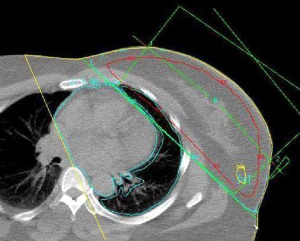

רוב המטפלים בסרטן השד על-ידי למפקטומיה משלבים טיפול קרינתי במנות של 6500R-5000R ויותר, כאשר חלק מהם (2000R) ניתן במרוכז על איזור (בוסט). עבודות שלא כללו קרינה כלל, הראו תוצאות פחות טובות מאשר הניתוחים הרדיקאליים, ולכן נראה שתנאי להצלחת הניתוחים המשמרים, הוא הוספת טיפול קרינתי לפרוטוקול. עבודות חדשות הראו שהקטנת מנת הקרינה ומשכה לא השפיעו לרעה על התוצאות לטווח ארוך ולכן בחולות שניתן להגדיל את המנה ולהקטין את מספר ההקרנות יקבלו אותו מינון מחולק ל-16 פעמים. גישה חדשנית לטיפול הקרינתי היא קרינה תוך ניתוחית. הרעיון מבוסס על כך שרוב החזרות המקומיות היו בסביבת הלמפקטומיה, ולכן יש להקרין את אותו איזור ולא את כל השד. בשיטה זו לאחר סיום הלמפקטומיה ולפני סגירת העור החולה מקבלת מנת קרינה בחדר ניתוח למיטת הלמפקטומיה, תהליך שנמשך כ- 45 דקות, ובסיומו העור נסגר מעל החלל. דווחים ראשוניים מראים שאין הבדל משמעותי בין החזרות המקומיות בחולות שקבלו קרינה על כל השד לבין אלה שקבלו קרינה רק למקום הלמפקטומיה.

כדי למנוע נזקי קרינה מידיים כמו כוויות על העור ונזקים מאוחרים כמו פגיעה בריאות ובלב יש לתכן את הקרינה בצורה כזו שהאיברים החיוניים יוצאו עד כמה שאפשר משדה הקרינה וכניסת הקרינה דרך העור תהיה כל פעם דרך מקום אחר (תמונה 41.12 ו-38.12).